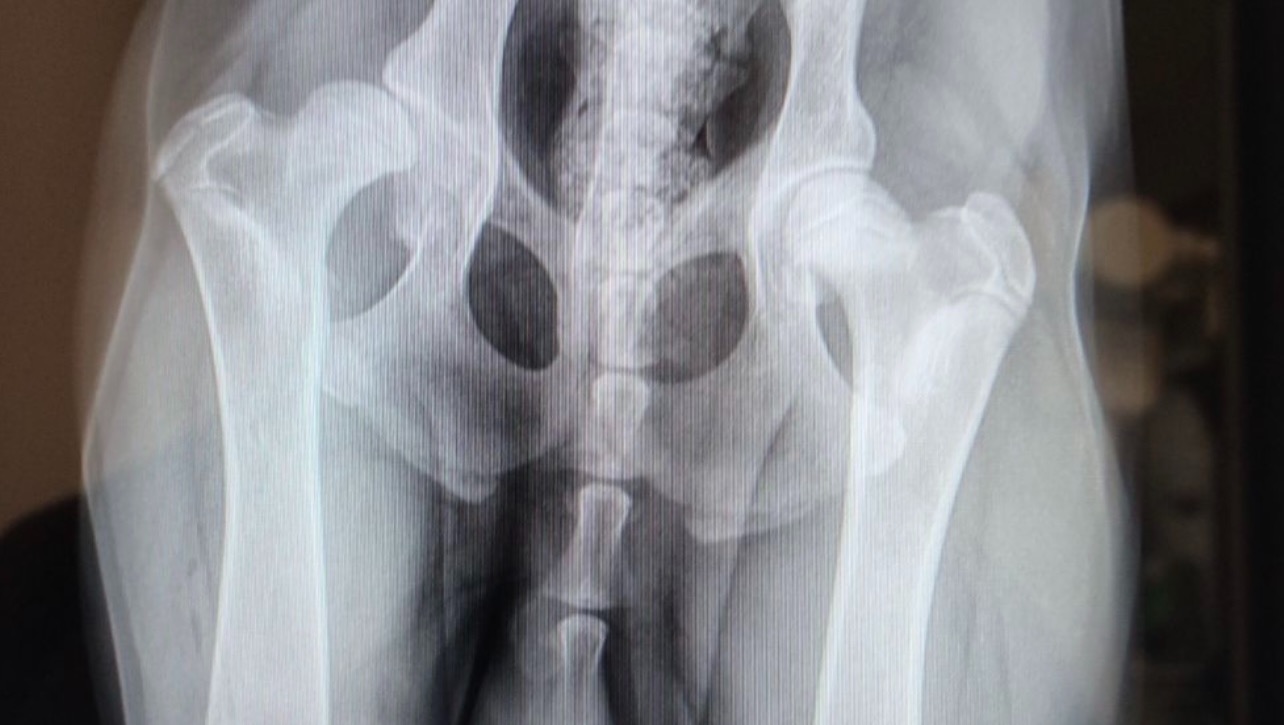

In June of 2021 I took Hanson to his vet because he was noticeably limping and didn’t want to put much pressure on his right foot. The after talking to his vet and after some X-Rays were taken, they came back saying that he showed signs of hip dysplasia at 5 months old. We were recommended a specialist and we went there in August of this year. The specialist recommended a total hip replacement surgery so Hanson can live a pain free life. This is a very expensive surgery around $5,000 that unfortunately our pet insurance won’t cover being that he is so young and we’ve had our insurance for less than a year. We scheduled the surgery in November of this year so he does not get any worse. Recovery time is around three months so by the time it is spring we will be able to start fresh with a brand new hip. Until then, he is on painkillers and restricted activity until he is able to go in for his surgery which is difficult being that he is such a high energy dog who loves to meet new friends. I am asking for donations to help offset the cost of his total hip replacement surgery. Hanson is so young and has so much life and potential ahead of him, so investing in his future is something that I feel is necessary.